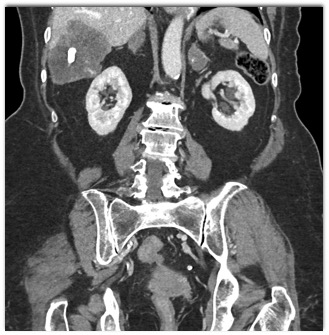

The best diagnosis in this patient with no known malignancy is?

hepatoma

metastatic colon cancer

sclerosed hemangioma

metastatic carcinoid tumor to the liver